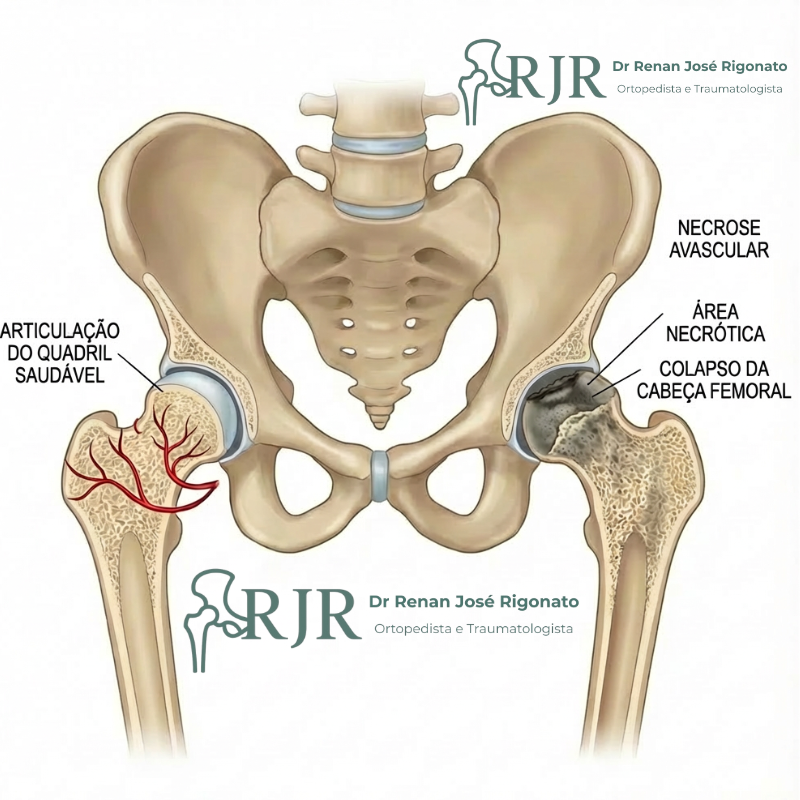

A osteonecrose da cabeça do fêmur, também conhecida como necrose avascular do quadril, é uma doença caracterizada por um defeito na circulação sanguínea da cabeça femoral, fazendo com que chegue pouco ou nenhum sangue a essa região. A falta de irrigação adequada leva à morte do tecido ósseo, comprometendo a estrutura do quadril.

O osso da cabeça do fêmur, assim como qualquer tecido do corpo humano, depende de um aporte sanguíneo adequado para receber oxigênio e nutrientes essenciais à sobrevivência de suas células. Quando ocorre a interrupção ou insuficiência do fluxo sanguíneo, o osso esponjoso da cabeça femoral — responsável pela sustentação e manutenção do formato esférico do quadril — perde resistência.

Com a progressão da doença, essa perda estrutural pode levar à deformação e colapso da cabeça do fêmur, resultando em dor no quadril, limitação dos movimentos e, frequentemente, evolução para artrose secundária do quadril.